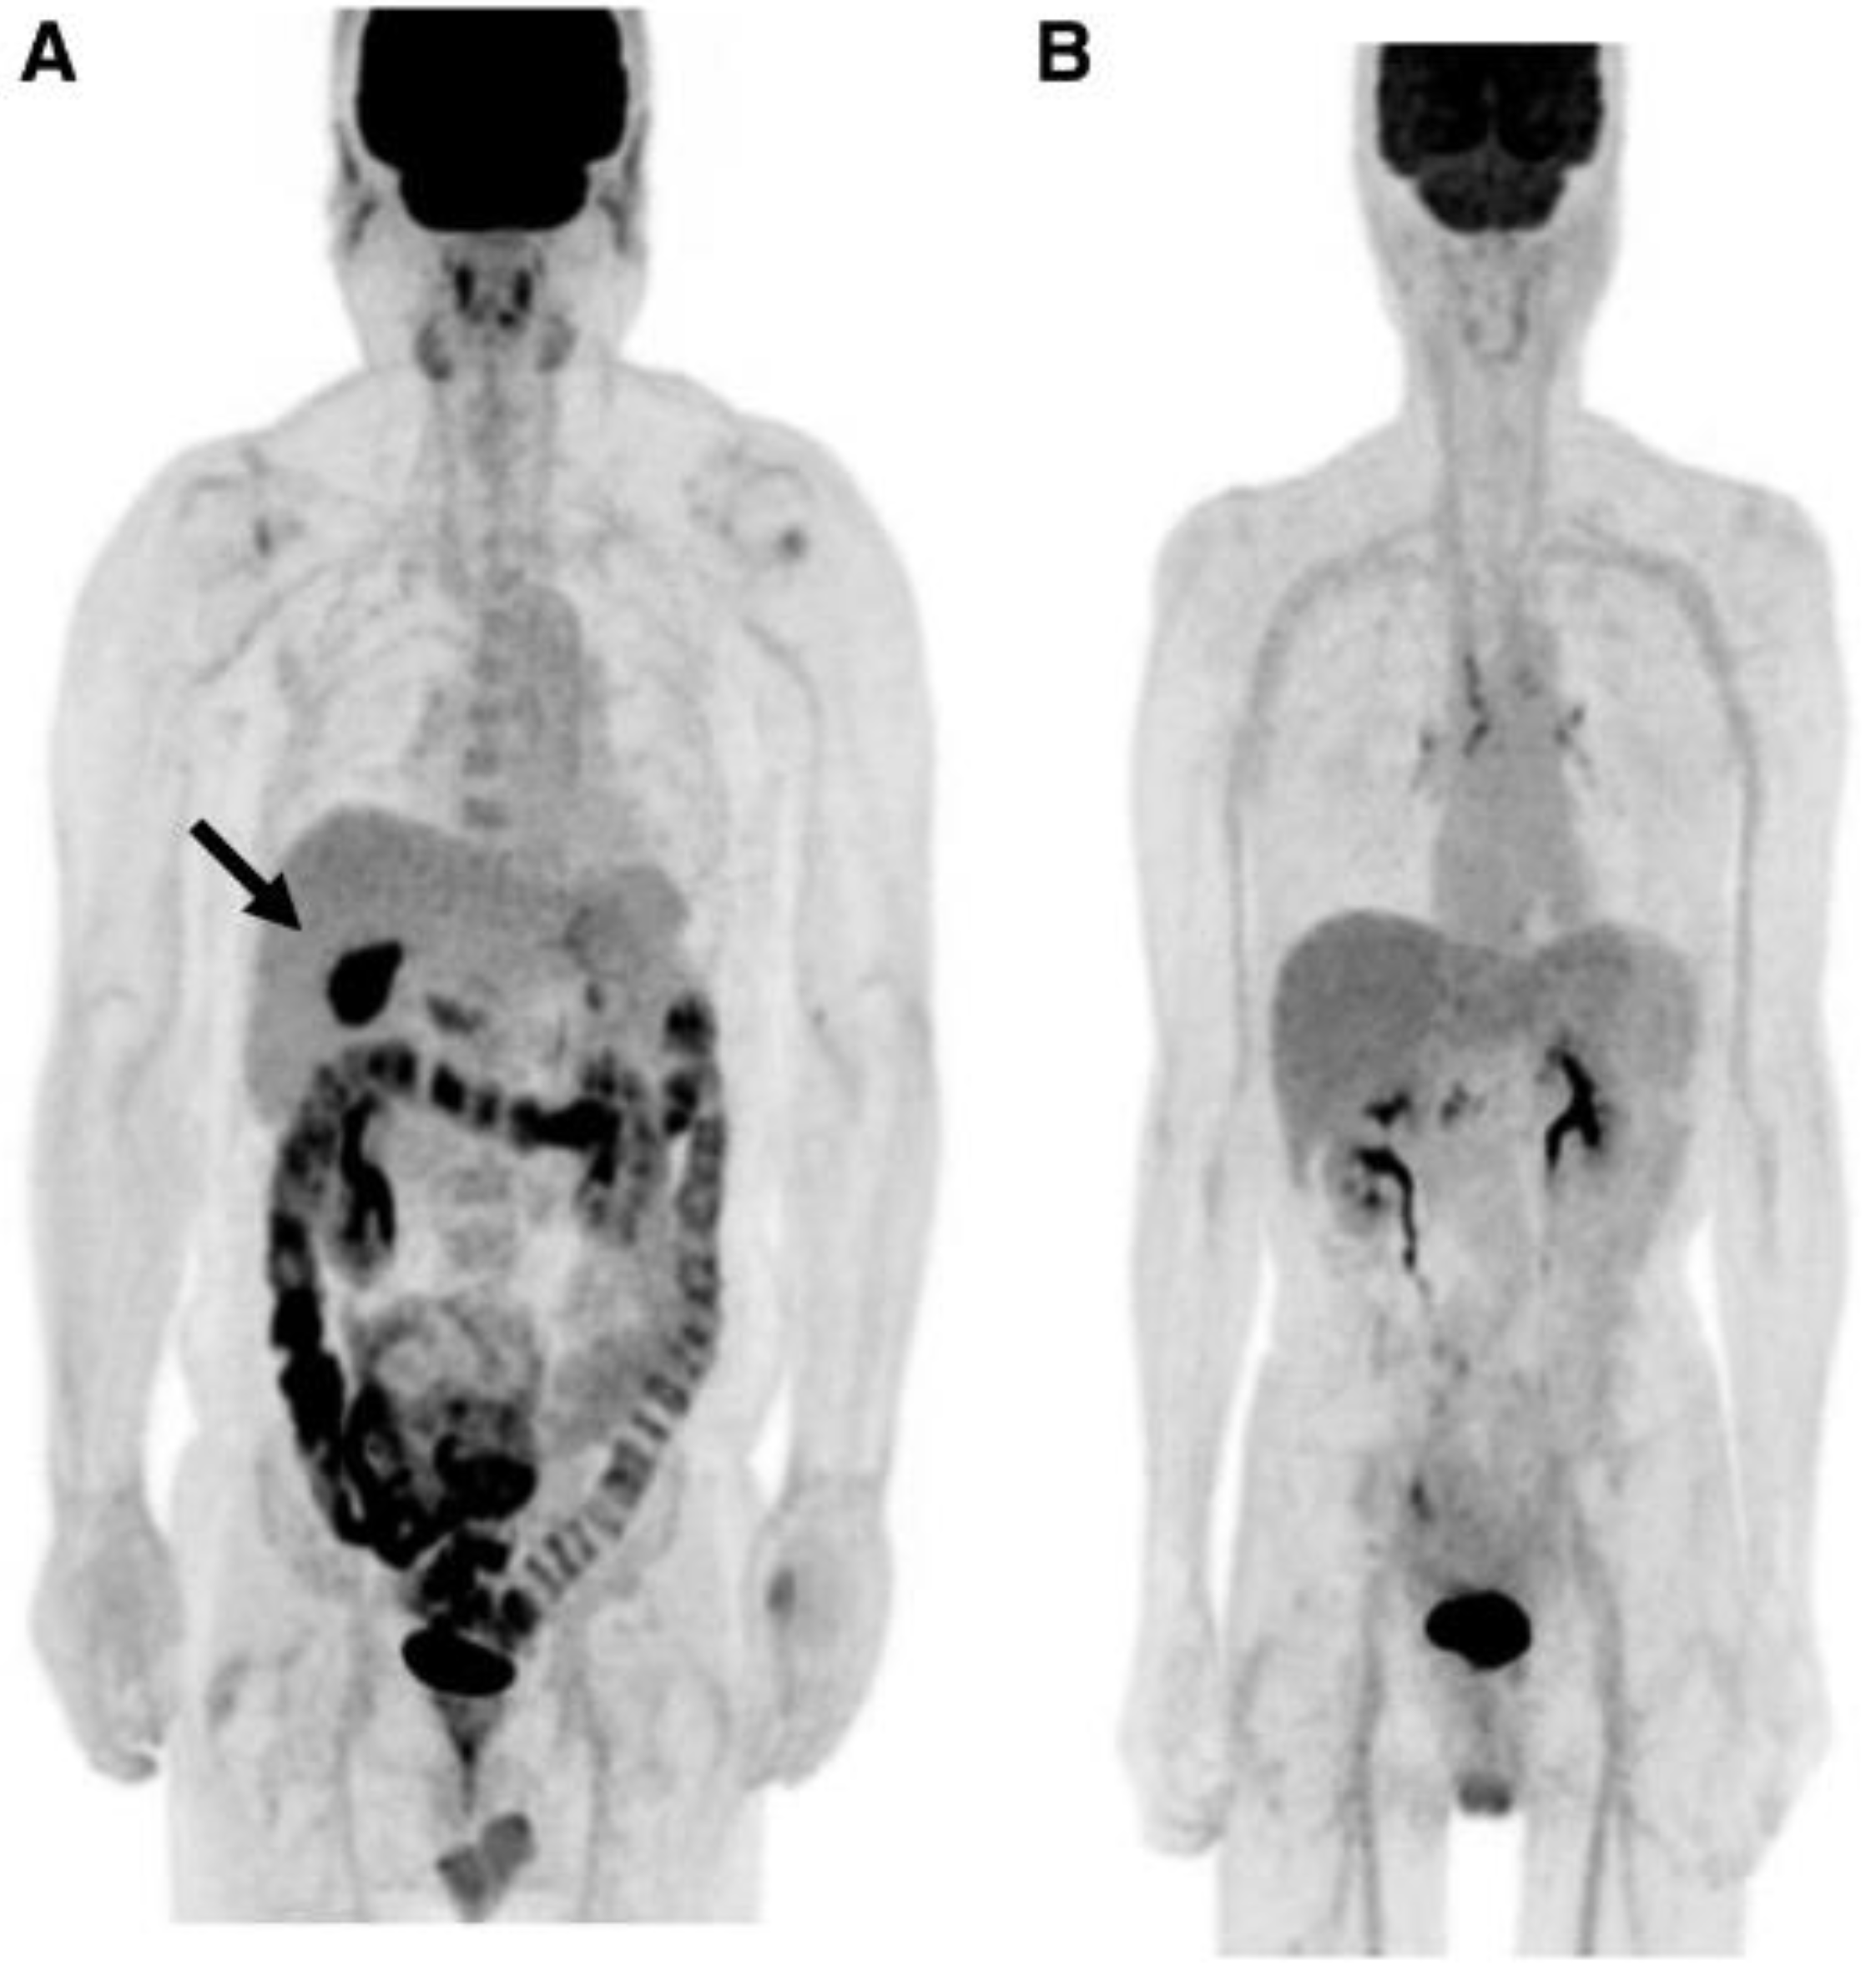

- 179..Kim S, Chung JK, Kim BT, Relationship between gastrointestinal F-18-fluorodoxyglucose accumulation and gastrointestinal symptoms in whole-body PET.Clin Positron Imaging 1999;2:273-279.

- Gontier E, Fourme E, Wartski M, Blondet C Bonardel G, Le Stanc E, Mantzarides M, Foehrenbach H, Pecking A-P, Alberini J-L.High and typical F18-FDG bowel uptake in patients treated with metformin.Eur J Med Mol Imaging 2008;35:95-99.

- Morita Y, Nogami M, Sakaguchi K, Okada Y, Hirota Y, Sugawara K, Tamori Y, Zeng F, Murokami T, Ogawa W.:Enhanced Release of Glucose Into Intraluminal Space of the Intestine Associated With Metformin Treatment as Revealed by [18F]Fluorodeoxyglucose PET-MRI.Diabetes Care 2020;43:1796-1802. [CrossRef]

- Özülkur T, Özülkur F, Mert M, Özpacaci T.Clearance of high intestinal F18-FDG uptake associated with metformin after stopping the drug.Eur J Nucl Med Mol Imaging 2010;37:1011-1017.

- Schreuder N, Klarenbeek H, Vendel BN, Jager PL, Kosterink JGW, van Puijenbroek EP.Discontinuation of metformin to prevent metformin-induced high colonic FDG uptake:is 48 h sufficient?.Annals of Neclear Medicine 2020;34:833-839.

- Massollo M, Marini C, Brignone M, Emionite B, Salani BRiondato M, Capitano S, Fitz F, Democrito A, Amaro A, Morbelli S, Piana MMaggi D, Cilli MPfeffer U, Sambuceti G.Metformin Temporal and Localized Effects on Gut Glucose Metabolism Assessed Using F18-DG PET in Mice.J Nucl Med 2013;54:259-266.

- Tu DG, Chen C-R, Wang Y-W, Tu C-W, Huang YC.Bowel-cleansing methods affecting PET-CT Image interpretation.Nucl Med Commun 2011;32:570-574.

- Chen Y-K, Chen J-H, Tsui C-C, Chou H-H, Cheng R-H, Chiu J-S.Use of Laxative-augmented Contrast Medium in the Evaluation of Colorectal Foci at FDG PET.Radiology 2011;259 (2):525-533.